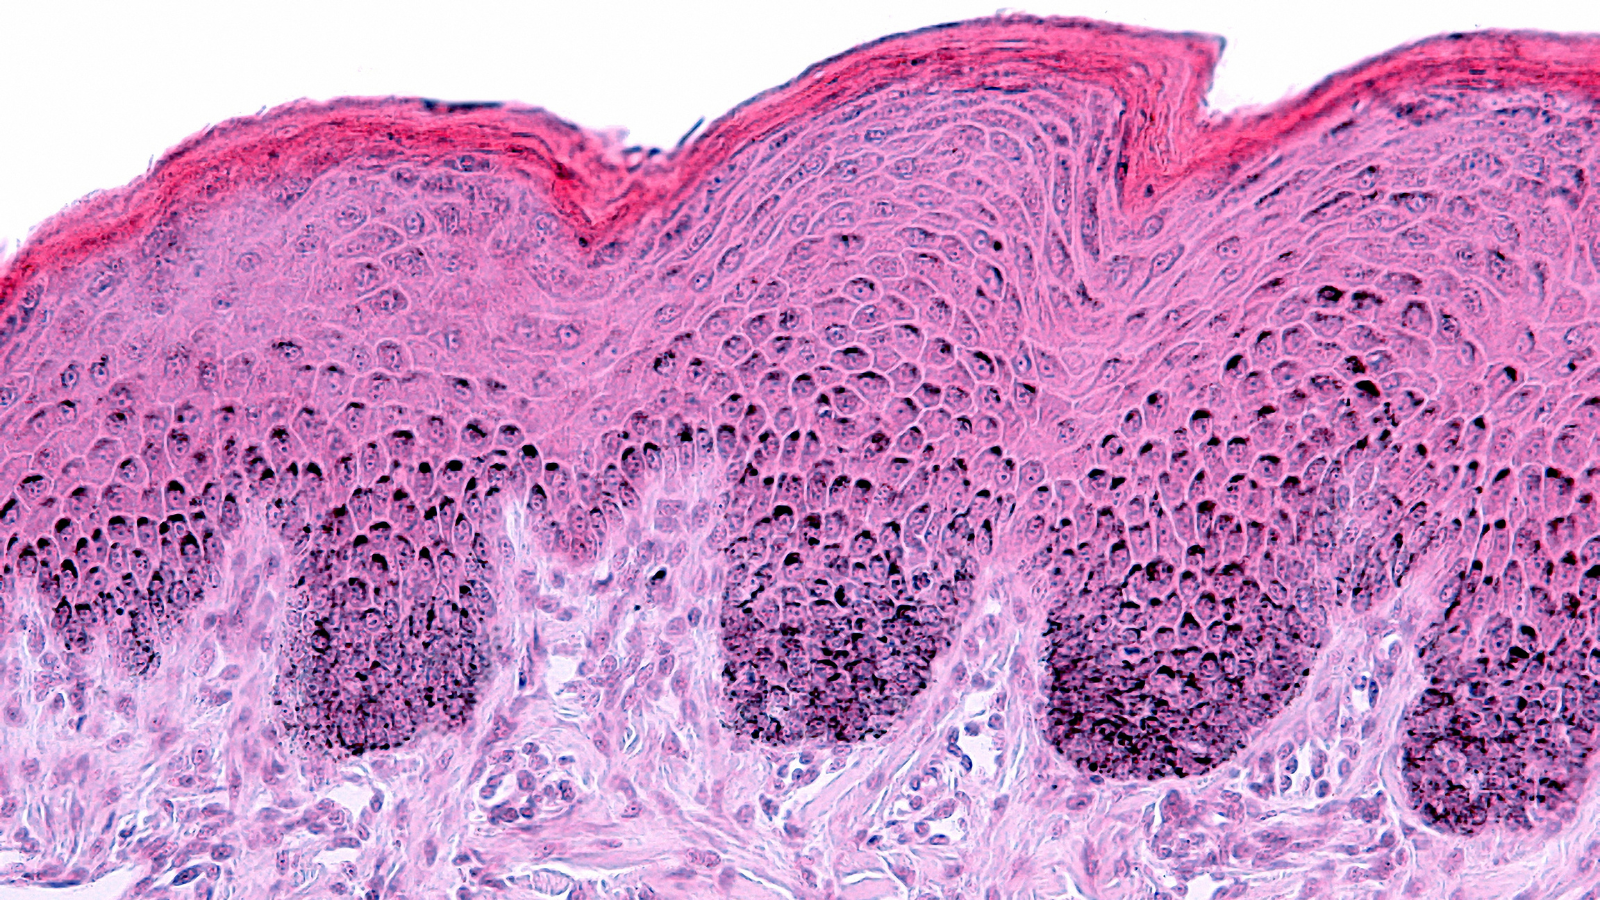

Humanity's quest for youthful, resilient skin stretches back thousands of years, from the natural oils and herbal remedies used by ancient civilizations to the evidence-based approaches of today. Modern science now recognizes skin longevity as more than just aesthetics. It encompasses the preservation of physiological integrity over time, supported by objective biomarkers and validated clinical endpoints.

Our new white paper examines the biological drivers of skin aging and details how advanced, non-invasive techniques are transforming clinical evaluation. By combining imaging, biomechanical assessment, biomarker analysis and hydration and barrier function measurements, researchers can now generate multi-dimensional data to scientifically substantiate product claims.